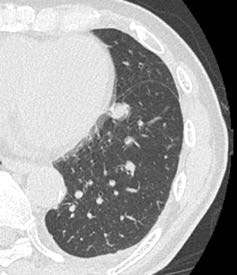

CLEAR Motionについては、CardiacとBodyの両方で使用している。稲垣係長は、「大動脈解離を疑い、従来であれば心電図同期が必要な症例でも、Aquilion ONE / INSIGHT Editionではガントリの回転速度やヘリカルスキャンも高速化していることに加えて、CLEAR Motionをかけることで心拍動によるアーチファクトを抑えて、ブレのない画像が得られます。スループットも向上しており、患者さんにとっても有用な検査が提供できます」と評価する。

CLEAR Motion OFF + Hybrid-IR CLEAR Motion OFF + Hybrid-IR

CLEAR Motion OFF + DLR CLEAR Motion OFF + DLR

CLEAR Motion ON + PIQE CLEAR Motion ON + PIQE

図2 原発性肺がん、肺転移症例で経過観察中

PIQE+ CLEAR Motionの併用で、心拍動に伴うアーチファクトを低減し、

高い時間分解能かつ高精細画像の両立が期待できる。